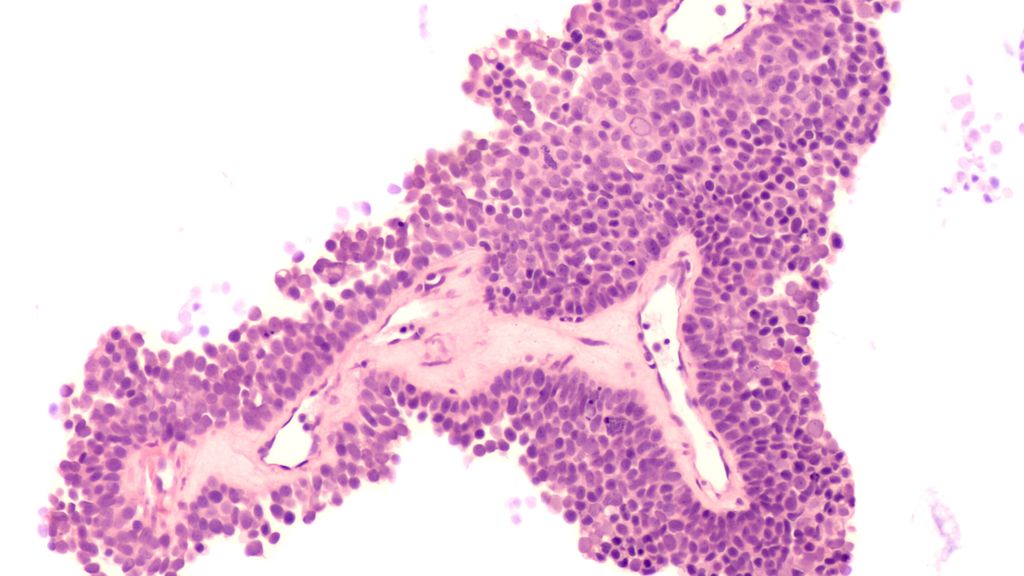

La prise en charge individualisée du carcinome mammaire est déjà très avancée dans la pratique clinique quotidienne. Néanmoins, des récidives tumorales surviennent et des patient·es ...

Le développement des conjugués anticorps-médicament («antibody-drug conjugates», ADC) a profondément modifié le traitement, en particulier du carcinome mammaire métastasé, et a nettement ...